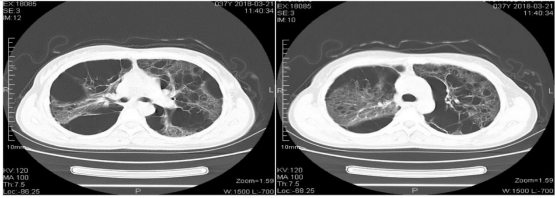

A 37-year old female was admitted to our hospital's gynecology department in 2018 with mild abdominal distension and pain for 2 months and a newly discovered pelvic mass for half a month. The chest CT scan at the hospital indicated diffuse lesions in both lungs (Figure 1). Gynecological ultrasound revealed a cystic mass (61x45mm) in the left adnexal region and pelvic fluid. Routine blood tests and vaginal infection panels were normal. The tumor marker CA125 was elevated at 45.4 ng/ml, while CEA, AFP, and CA199 were normal. Repeat ultrasound showed "Cystic mass in left adnexa: Hydrosalpinx? (84x49mm), Pelvic fluid." Exploratory laparotomy and mass excision were performed. Intraoperatively, the uterus and bilateral adnexa appeared normal, but the left broad ligament was enlarged (approx. 6x5x4 cm), cystic, and adherent to the bowel via membranous adhesions. Postoperative pathology was reported as "leiomyoma"(Figure 2). Forty days postoperatively, the patient developed ascites. Chylous fluid was drained via culdocentesis (Figure 3). Ascites analysis showed a positive Rivalta test, +++ red blood cells, and LDH 162 U/L. Reviewing her history, she had undergone resection for "pulmonary cysts" at another hospital in 2013, which was misdiagnosed as pneumothorax pathology.

Chest CT at hospital : "1. Diffuse, multiple, variably sized cystic lucencies in both lungs, with thickened lung interstitium and multiple linear opacities. No significant pleural

effusion."